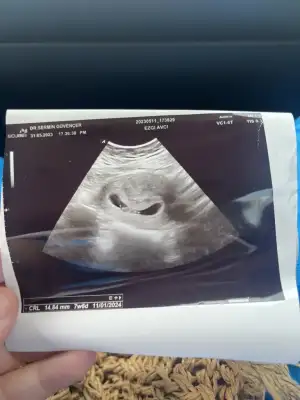

Selam benim de 5+3 falan olması lazım daha gitmedim haftaya pazartesi gideceğim o zamana kadar görünür hale gelir diye düşünüyorum. 6+2 olacak kalp atışını da duyarım belki. Siz de eğer giderseniz yazın keseyi görüp görmediğinizi ben de merak ediyorum. 🙏

Merhabalar. Ben bugün gittim 5+2 yim. Kese göründü canım